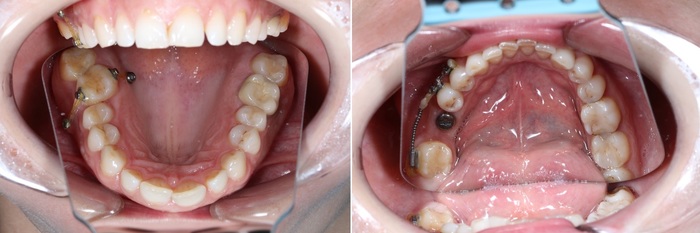

Константин пунктуально прибыл в намеченный день и час. 3 июня 2023. Осмотрев полость рта и «заколдованное» место, в частности, я предложил начать. Константин согласился, хоть и немного волновался. Но это и немудрено после всего того, что он прошёл.

Конечно, меня посещали мысли, что же там такого, что первый раз почти 6 часов пытались удалить зуб, а во второй вообще ёбанули нерв. Сделал анестезию, разрез, и удалил зуб за 4 минуты.

Уточняю: 3 минуты ждали, пока подействует анестезия, 4 минуты удаляли зуб, 5 минут накладывали швы, 3 минуты я катал Константина в кресле вверх и вниз. Всё. Меньше 15 минут ушло на удаление остатков зуба мудрости. На целый ушло бы не больше 25.

Белые точки – это остатки йода от йодоформной турунды, которую уложили в больнице (если вы читали выписку). Он рентгеноконтрастен.